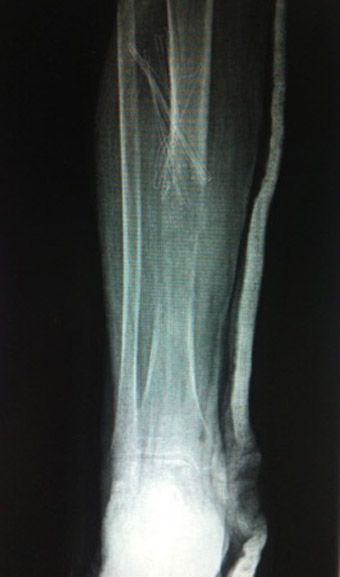

Mujer de 63 años que inicia un dolor en cara anterior del tercio medio de la tibia, sin traumatismo previo, el dolor tras dos meses no mejora con medicación analgésica convencional. Tras una deambulación prolongada presenta dolor más intensa e impotencia funcional. Acude a urgencias donde en el estudio radiográfico (foto 1) se aprecia una fractura sobre lesión lítica. Dada la edad de la paciente se realiza una biopsia ósea por sospecha de lesión metastásica y se diagnóstica de tumor primario ginecológico con metástasis única en tibia a nivel del tercio medio.

Foto 1. Radiografías anteroposterior y lateral de la tibia, donde se aprecia una fractura patológica del tercio medio/distal de la tibia. Sobre una lesión lítica.